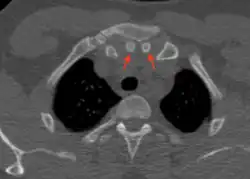

Episternal ossicles

Episternal ossicles (or suprasternal ossicles) are small bones that are sometimes present at the upper end of the chest bone. The prevalence of these ossicles is around 1.5%.[1]

The episternal ossicles are oval-shaped bones that are occasionally found at the superior and posterior border of the manubrium. The episternal ossicles were first described by Cobb in 1937.[2] They may be present unilaterally or bilaterally.[3] Its size ranges from 2–15 mm depending on individuals.[4] These ossicles are asymptomatic and does not cause any harm, although it may be diagnosed as fracture, vascular ossification or calcified lymph nodes.